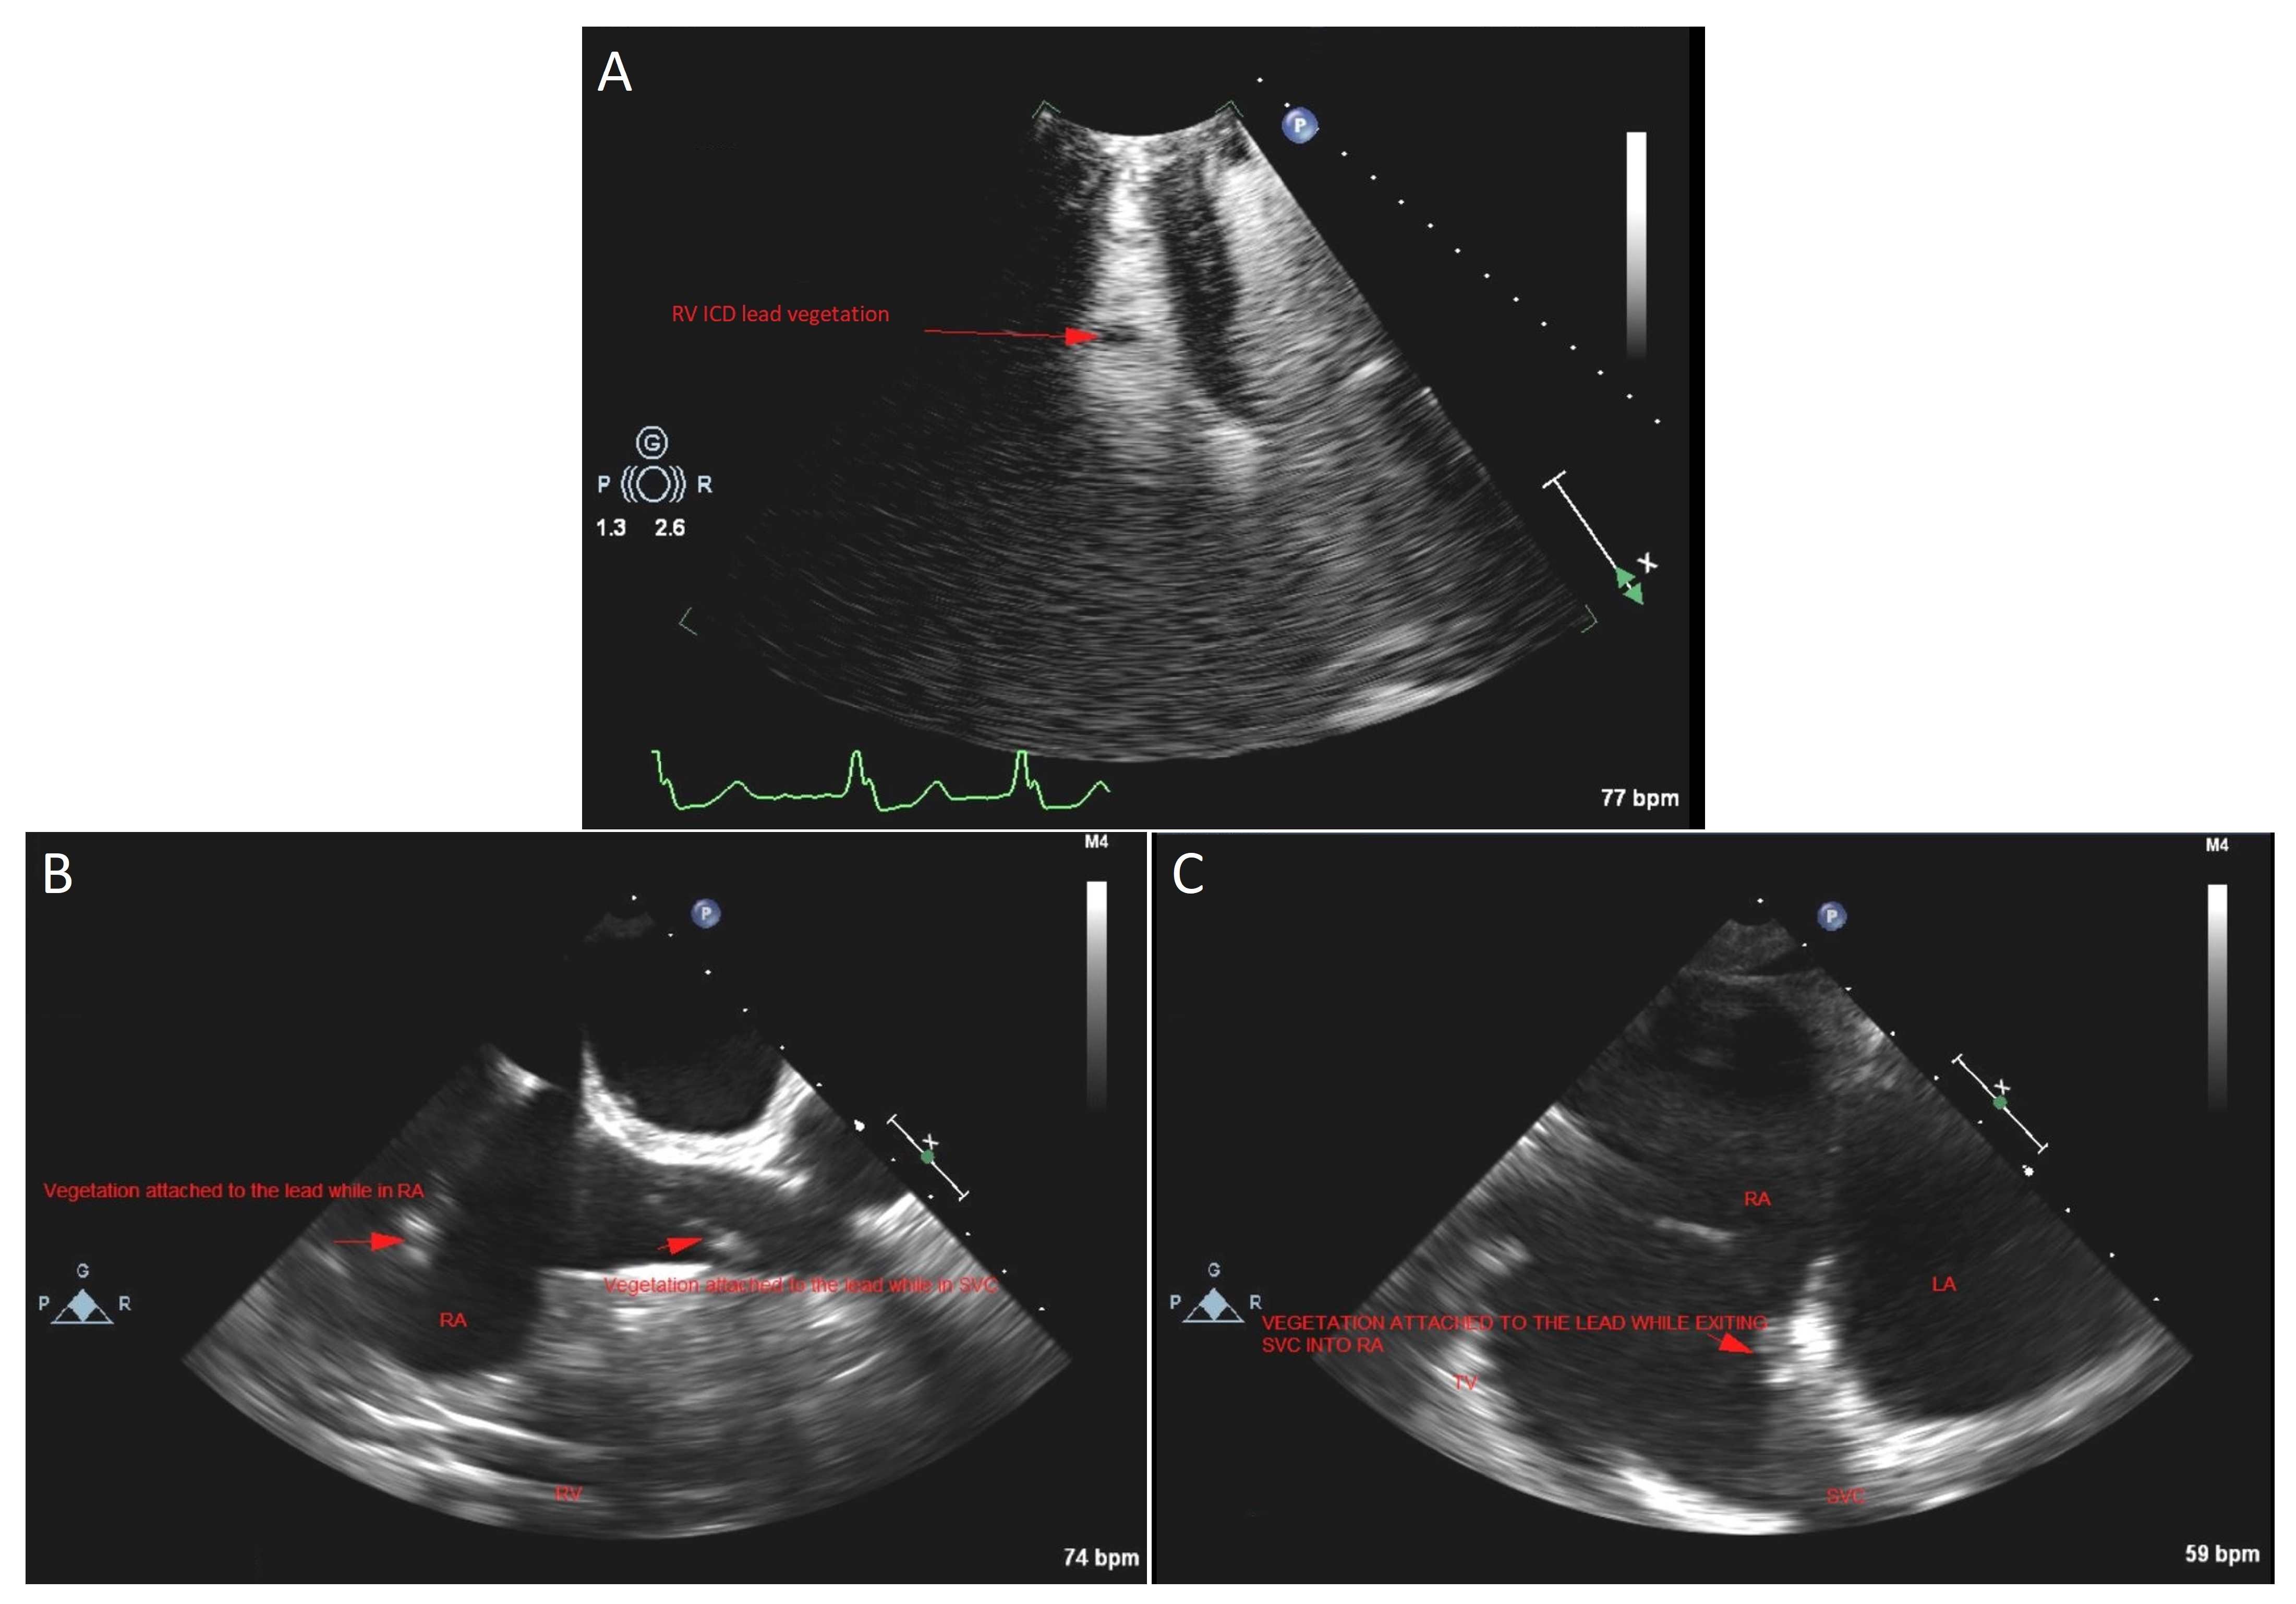

2. Case Presentation